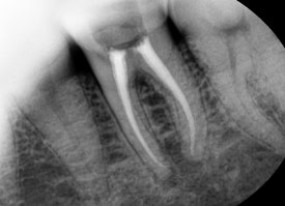

1. Is the preservation of natural teeth the top priority?

Unlike other parts of our body, teeth do not regenerate after being lost.

Therefore, before deciding to extract a tooth, it's important to carefully consider various preservation treatment options and determine the direction of treatment.

Of course, if inflammation is affecting surrounding teeth, the situation is different. However, it's best to choose a clinic with a 'treatment philosophy' that prioritizes tooth preservation.